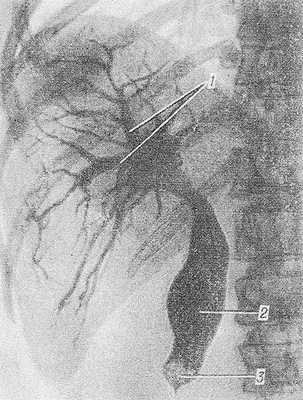

Рис. 1. Чрескожная чреспеченочная холангиография при желчнокаменной болезни (прямая проекция): желчные протоки (1) и общий желчный проток (2) расширены, в дистальной части общего желчного протока имеется окклюзирующий камень (3).

Чрескожная чреспеченочная холангиография получила распространение, когда появились сверхтонкие иглы для пункции внутрипеченочных протоков, обеспечивающие доступность и относительную безопасность искусственного контрастирования желчных путей. Основные показания — уточнение локализации, природы и характера окклюзии желчных протоков у больных желтухой, вызванной камнем, стриктурой, опухолью, когда невозможно проведение ретроградной холангиографии. Противопоказания — гнойный холангит, геморрагический диатез, резкие нарушения свертывающей системы крови. После премедикации (см. Наркоз) и местной анестезии (см. Анестезия местная) производят чрескожную пункцию брюшной стенки в восьмом межреберье по передней подмышечной линии. Если желчные протоки расширены, что устанавливают предварительно с помощью компьютерной томографии (см. Томография компьютерная) или ультразвукового сканирования (см. Ультразвуковая диагностика), то иглу направляют в периферические отделы печени; при нерасширенных протоках — в сторону ворот печени. Пункция расширенных протоков удается почти всегда, а нерасширенных — у 80—85% больных. Под контролем рентгенотелевидения (см. Телевидение в медицине) конец иглы устанавливают в просвете одного из внутрипеченочных желчных протоков и по ней вводят необходимое количество (от 20 до 60 мл) трийодированного рентгеноконтрастного вещества (см.), после этого производят рентгенограммы в прямой и косых проекциях (рис. 1). Терминальную часть общего желчного протока исследуют в вертикальном или полувертикальном положении больного. Процедура диагностического исследования может перейти в лечебную, если обнаружены расширенные желчные протоки и возникают показания к их временному или постоянному дренированию. Если при обнаружении гипертензии желчных протоков сразу же выполняется их дренирование, то осложнения наблюдаются редко. К ним относятся: истечение желчи или крови в брюшную полость, гемобилия (см.), случайное ранение органов грудной или брюшной полости. Для предотвращения септических осложнений рекомендуется введение антибиотиков за 1 час до процедуры и после нее.